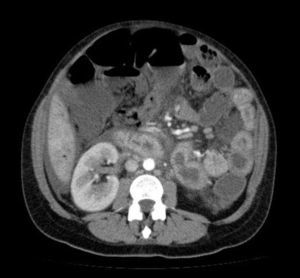

Caso clínicoSe trata de una paciente de 37 años que, 12 horas después de un parto vía vaginal sin complicaciones, comenzó con dolor abdominal inespecífico, náuseas, vómitos y fiebre alta, siendo tratada con analgésicos y antitérmicos habituales. Se realizó Rx abdominal, que mostró neumatización gástrica y de ciego, con distensión de este último, presencia de gas en ampolla rectal, y múltiples niveles hidroaéreos, sugestivo de íleo paralítico (fig. 1). Doce horas después, la paciente comenzó con hipotensión mantenida y oliguria refractarias al tratamiento con sobrecargas de volumen, por lo que se decidió ingreso en la UCI.